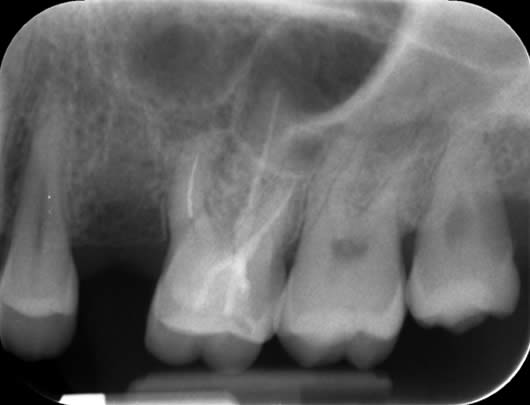

Case 7: Root canal retreatment – a good healing outcome.

In this case, the patient presented with a ‘blister’ in the gum next to her lower right first molar (LL6). The LL6 had a crown and was tender when tapped. There was a small swelling in the gum with a communication, which we call a sinus. We placed a tracer cone within the ‘blister’ and took a radiograph to see where the infection was draining from. This showed that the tooth had a root filling in the canals and a large shadow around one of the roots. The tracer cone was pointing to this large shadow indicating that this was the source of the ‘blister’. It was clear that the previous root canal treatment had failed and it was thought that the reason for the failure was persistent infection or reinfection of the canals. After discussion of treatment options, we decided to do root canal retreatment. The previous root canal filling was removed from all canals. The canals were then shaped, cleaned and filled again. In between the two treatment visits, the ‘blister’ had healed. We reviewed the tooth one year later and the patient reported that the tooth had been fine. We took a radiograph and could see that the ‘shadow’ had gone and the lesion had filled with new bone.

Before our treatment- the canals contain the root filling from the previous treatment. The tracer cone is pointing to the large ‘shadow’.

After completion of root canal retreatment